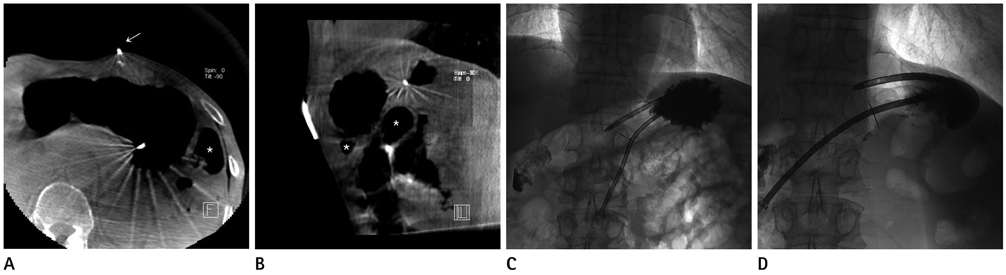

Figure